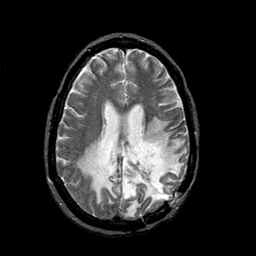

MR Study #1 -- Slice #34